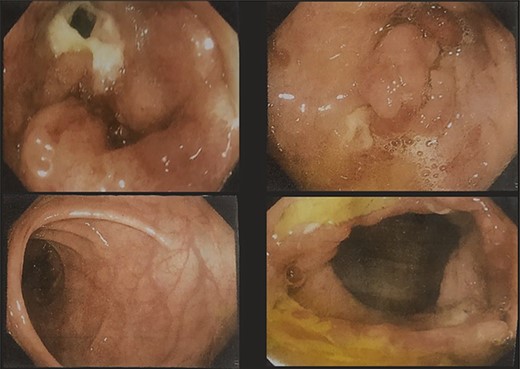

A 51-year-gentlemen and a smoker visited our institute with a history of abdominal pain, predominantly over the umbilical area, constant in nature, associated with anorexia, back pain and occasional chest pain for about 1 year. Besides pallor, other examination findings were grossly normal. His body mass index was 17 mg/m2. The comprehensive blood panel, renal function test and liver function test yielded normal findings. USG of abdomen and pelvis showed thickened cecum and terminal ileum with few adjacent mesenteric lymph nodes likely to be an infective/inflammatory pathology along with coexisting right nephrolithiasis. Intestinal TB was suspected and further investigations were done but reported negative Mantoux test, AFB smear and normal chest X-ray findings. Colonoscopy showed ulcero-proliferative growth in the cecum and descending sigmoid junction with punch biopsy from the cecal growth showing mitotic lesion suggestive of carcinoma colon (Fig. 1). A repeat colonoscopic biopsy of the cecal growth suggested diffuse active colitis. Computed tomography (CT) revealed segmental asymmetrical circumferential mass-like wall thickening of the cecum and ascending colon over the length of 7.6 cm causing luminal narrowing with enhancing soft tissue extension into the adjacent pericolic fat with loss of fat plane with the right psoas major muscle, pericolic fat stranding along with thickening of adjacent peritoneal lining (Fig. 2). The presence of multiple homogeneously enhancing pericolic, ileocolic, superior mesenteric artery and para-aortic groups of lymph nodes suggested colon carcinoma (T4aN2b). It also revealed a small iso-dense lesion showing homogeneous enhancement on the arterial phase in segment VII of the right lobe of the liver abutting capsule suggestive of metastasis. Carcinoembryonic antigen (CEA) was found to be slightly raised (7 ng/dl).

CT images showing segmental asymmetrical circumferential mass-like wall thickening of the cecum and ascending colon over the length of 7.6 cm causing luminal narrowing with enhancing soft tissue extension into the adjacent pericolic fat with loss of fat plane with the right psoas major muscle, pericolic fat stranding along with thickening of adjacent peritoneal lining.